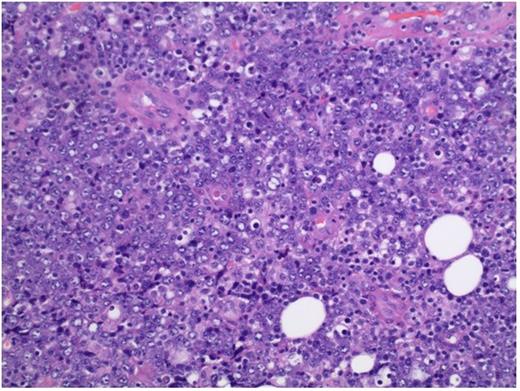

H&E section showing a monomorphic proliferation of malignant cells with large immunoblastic tumor cells with prominent nucleoli. Magnification 20X.

44 year old male with no past medical history presents with rapidly enlarging neck mass over past two months. He denied B-symptoms. Clinical examination revealed bulky midline neck mass with bilateral cervical and left supraclavicular adenopathy. 6/29/16 excisional lymph node biopsy of neck lymph node showed a monomorphic proliferation of malignant cells with large immunoblastic tumor cells with prominent nucleoli (Figure1). Neoplastic cells expressed MUM-1, CD138 (Figure 2), and were lambda light chain restricted. Neoplastic cells were negative for CD20, CD79, CD3, CD5, CD7, and BCL-2. Additionally, Cyclin D1, BCL-6, CD30, ALK-1, S100, CD56 was negative. Ki-67 was 99%. EBER by ISH was positive (Figure 3). Karyotype was normal. PET CT 7/1/16 Showed small hypermetabolic lymph nodes in the right neck, bilateral parotid gland with additional hypermetabolic activity in the left supraclavicular fossa and central neck base along with activity in the tongue base with maximum SUV 16.1. CT neck chest abdomen and pelvis 7/1/16 showed bilateral enhancing parotid lesions, large central midline neck mass with right strap muscle involvement. Also, there was soft tissue prominence of the adenoids, tonsil pillars, lingual tonsils, laryngeal ventricle. Last there was bilateral deep cervical, supraclavicular, & posterior cervical lymphadenopathy. Lumbar puncture, bone marrow biopsy, & MRI brain were negative for involvement. Labs 6/27/16: Platelet 126 10x3/µL, hemoglobin 15.7 g/dL, white blood cell 5.2 with variant lymphocytes. Uric acid 4.3 m/dL, total protein 9.3 g/dL, creatinine 1.23 m/dL, alanine aminotransferase 83 U/L, aspartate aminotransferase 83 U/L and complete metabolic panel otherwise normal. LDH 228 U/L, beta 2 microglobulin 4.5 mg/L. HIV-1 test was positive with 94316 copies/mL by PCR. CD4 count 65 cells/mcl. EBV VCA IgM <0.2 AI, EBV VCA IgG > 8.0 AI. IgG 3023 mg/dL, IgE 207IU/ML, IgA 581 m/dL, IgM 286 mg/dL, free kappa 117 mg/L, free lambda 97.94 mg/L and normal kappa/lambda ratio. SPEP with immunofixation consistent with inflammatory response. Peripheral blood flow cytometry revealed a minimal kappa predominant monoclonal B-cell population. Patient started on DA-EPOCH with prophylactic intrathecal methotrexate with excellent clinical response after first cycle. Plan for 4-6 cycles with prophylactic intrathecal chemotherapy followed by autologous stem cell transplantation. For supportive care, the patient was started on HAART therapy, acyclovir, fluconazole, Levaquin, azithromycin. To our knowledge this is the first case of bilateral parotid gland involvement in PBL. Furthermore it is unclear if the hypergammaglobulinemia is related to HIV infection vs. directly PBL related.